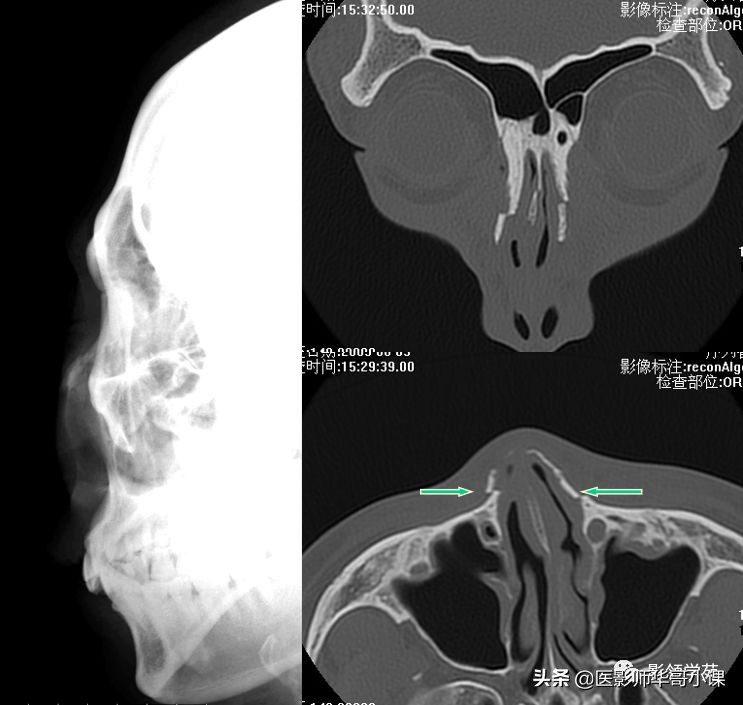

检查方法

X线平片:侧位

HRCT

鉴别诊断

- 鼻缝

- 鼻骨孔

- 缝间骨

鼻颌缝

鼻额缝

额颌缝

鼻骨间缝

鼻骨孔

缝间骨